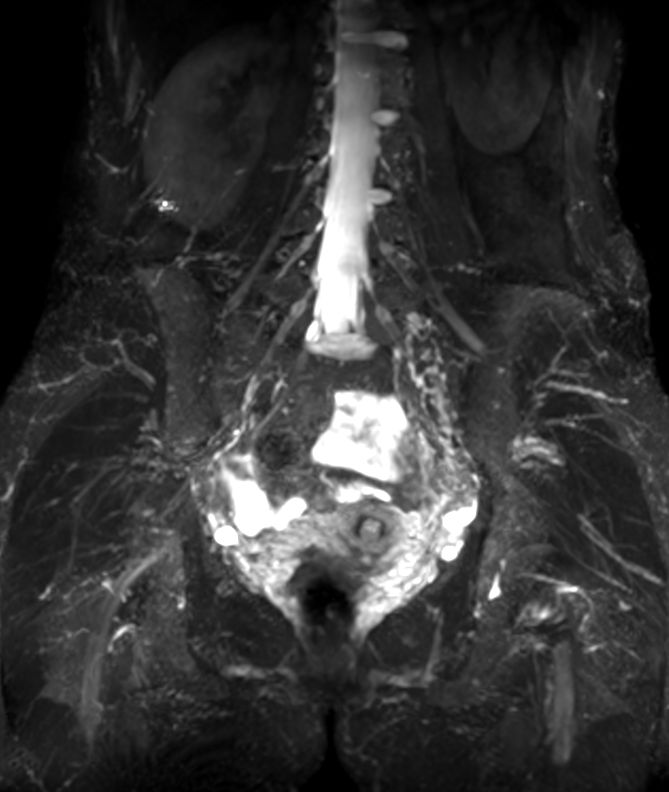

Lumbar Plexus imaging

• Clinical Application